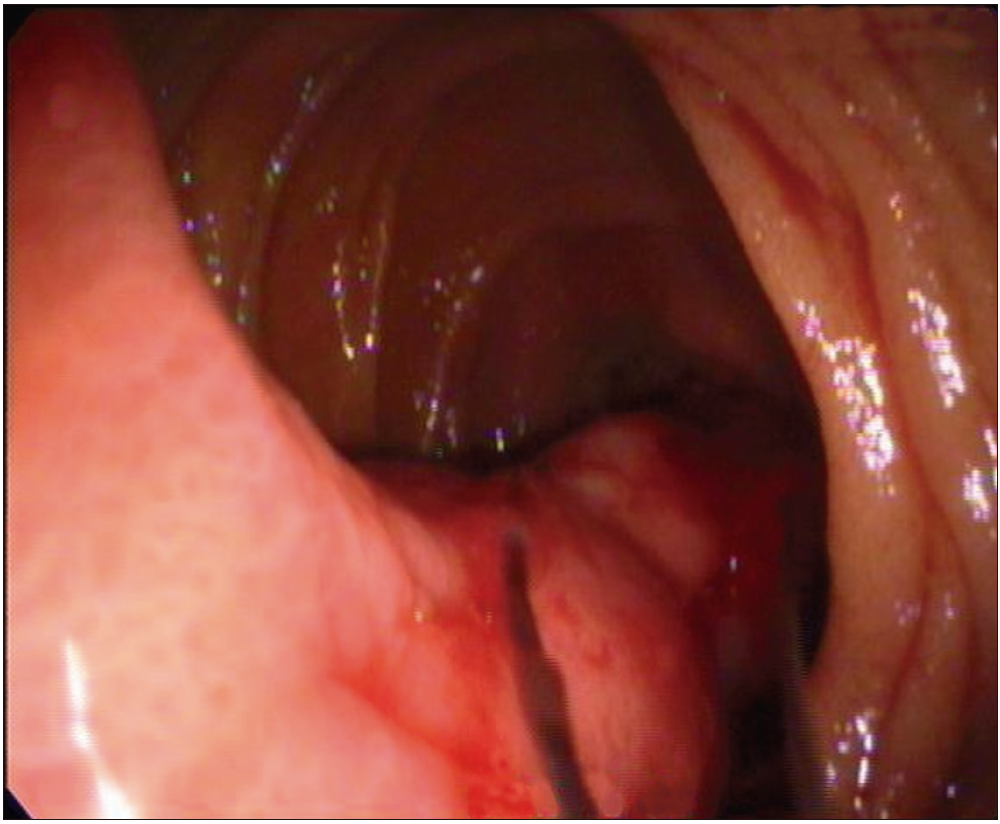

Paciente masculino de 56 años de edad, que consultó por melena de 48 horas de evolución. Ingresó hemodinámicamente estable con una hemoglobina de 9,2 g/dl (valores previos de 13,1 g/dl). Como antecedentes refirió dos episodios previos de hemorragia digestiva alta a los 54 años de edad, que fueron estudiados en otra institución sin encontrar la causa del sangrado. Se realizó una videoendoscopía digestiva alta que evidenció una lesión polipoidea subpediculada de superficie erosionada de aproximadamente 5 cm, ubicada en la tercera porción duodenal. (Figura 1 y 2).

Figura 1. Videoendoscopía digestiva alta. Lesión polipoidea subpediculada de

superficie congestiva de aproximadamente 5 cm ubicada en la tercera porción duodenal